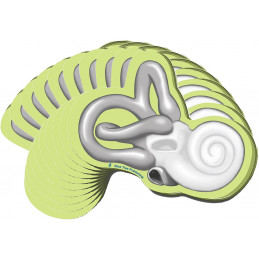

The Ear tear off tablet illustrates anatomy of the ear with QR code link to animation

These cochlea-shaped, self-stick notes illustrate the cochleas's exterior in detail